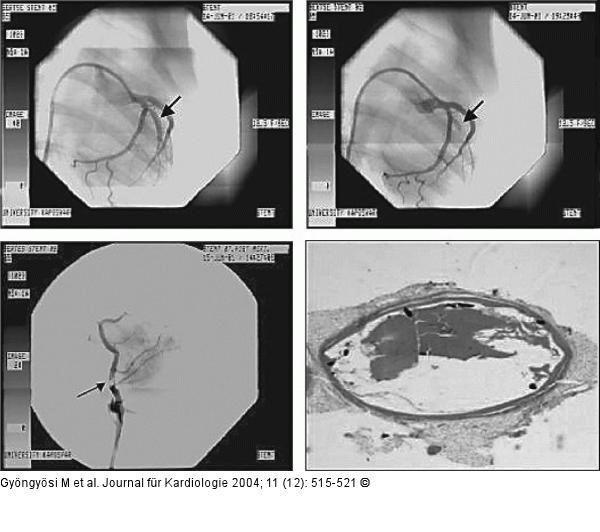

Abbildung 4: Stentthrombose Akute Stentthrombose eine halbe Stunde nach Stenting des großen diagonalen Astes bei einer Angiographie (links oben). Post-mortem-selektive Angiographie der Arteria circumflexa (links unten) zeigt eine akute Stentthrombose. Histologischer Nachweis der akuten Stentthrombose (rechts unten). |